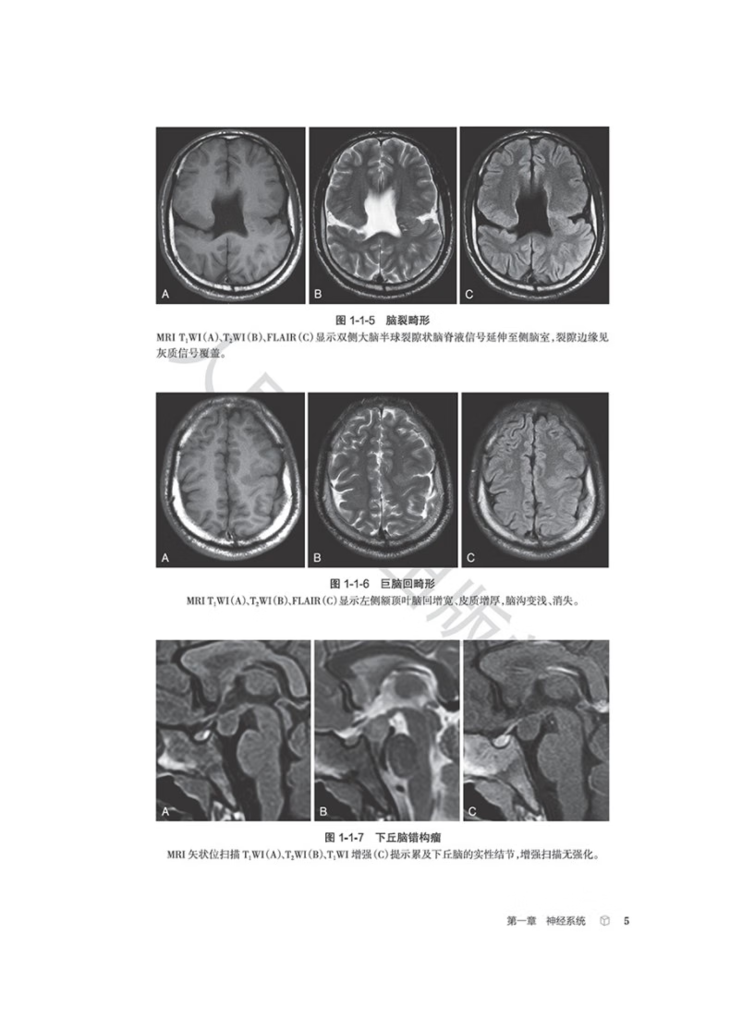

生殖系统、骨关节等影像科日常工作中的近300个常见征象,从每个征象的分析入手,凝练影像征象的特征,辅

以征象典型图进行说明,应用思维导图展现征象分析和诊断的思路,并融入鉴别诊断点和相应的疾病谱,抽丝剥

茧,去伪存真,示范从影像征象到诊断疾病的思维过程。